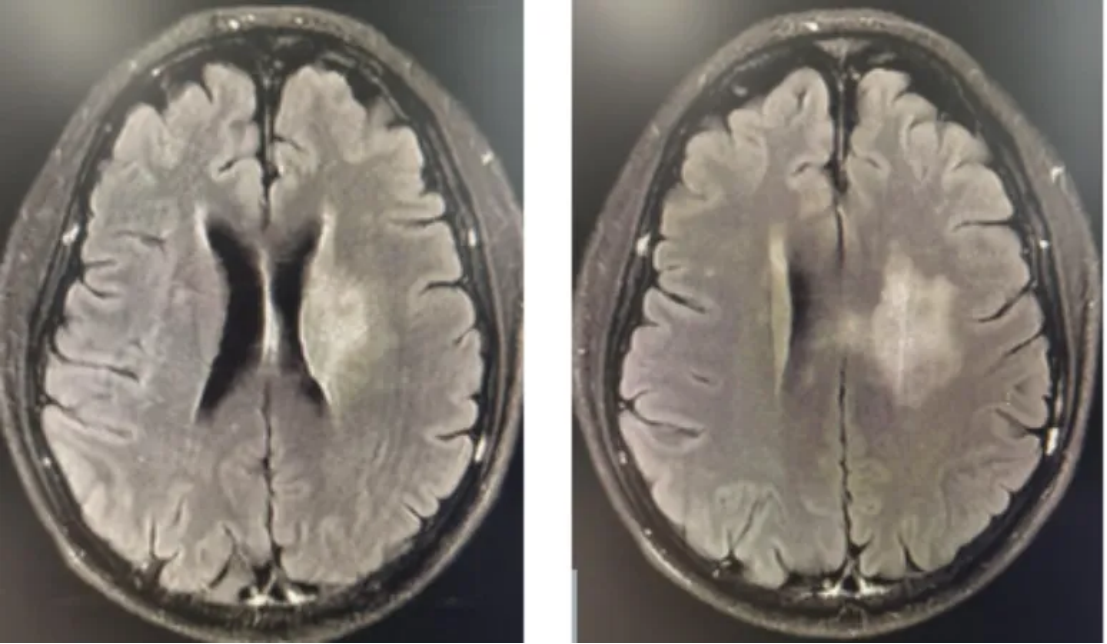

2024-05-19复查颅脑MR:对比2024-01-27 MR(图3):中脑不规则异常信号影,符合DMG治疗后改变,较前变化不大。左侧颞叶海马区、左侧丘脑、侧脑室旁条片状异常信号影,符合DMG表现,范围较前增大,提示肿瘤进展(图4)。

图3 2024-01-27复查影像学

图4 2024-05-19复查影像学